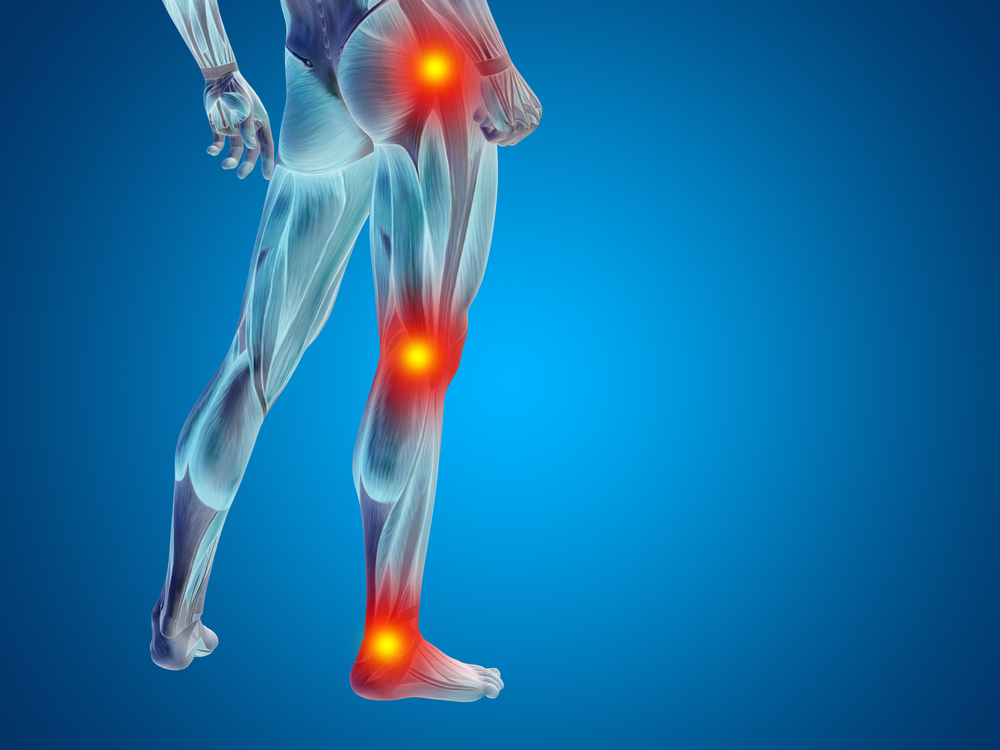

Inverno pode acentuar as dores nas articulações do joelho e quadril

Com a chegada do inverno e a queda nas temperaturas, muitas pessoas com problemas articulares como a artrose de joelho e quadril e de vascularização podem sentir mais dores neste período do ano.

O motivo é porque em épocas geladas, as pessoas costumam ficar mais encolhidas e se movimentam menos, o que causa algum grau de rigidez articular e, consequentemente, dor. O corpo humano, para funcionar bem, deve ser mantido a uma temperatura interna entre 36°C e 37°C —tarefa nada fácil quando os termômetros marcam menos de 10°C, por exemplo. Para se defender do frio, o músculo se contrai involuntariamente. Com isso, a circulação sanguínea entre tecidos, pele e articulações fica comprometida. Isso também causa dor e espasmos.

O médico vascular Gustavo Junqueira, do Eco Medical Center, explica que no inverno os vasos sanguíneos se contraem em um processo chamado de vasoconstrição, especialmente nas extremidades do corpo, como mãos e pés. “Essa vasoconstrição é uma resposta do corpo para evitar a perda excessiva do calor, mas essa condição pode reduzir o fluxo sanguíneo nessas áreas, resultando em uma menor oferta de oxigênio e nutrientes para o tecido, o que aumenta as dores e dificulta a mobilidade”, afirma.

A rigidez articular também é um sintoma recorrente no inverno.“O líquido sinovial, responsável por lubrificar as articulações, fica mais viscoso com o frio, tornando essas articulações mais dolorosas”, reforça o médico vascular.

Qualquer pessoa pode ter sensibilidade à dor no frio, mas as dores são mais acentuadas durante o inverno em pacientes com lesões degenerativas crônicas, como artrite e artrose e também lesões inflamatórias, como tendinites e tendinopatias.

O ortopedista e especialista em cirurgia do joelho, Rogério Fuchs, explica que a chegada de menos sangue e nutrientes aos músculos e articulações no frio faz com que essas estruturas fiquem com o metabolismo prejudicado e com uma dificuldade ainda maior de combater qualquer processo inflamatório. “Pessoas com problemas ortopédicos também sentem mais, porque a temperatura tem efeito sobre os ossos das extremidades”, reforça. Ele orienta que pacientes com problemas articulares e doenças degenerativas devem procurar o atendimento adequado, especialmente nesta época do ano.